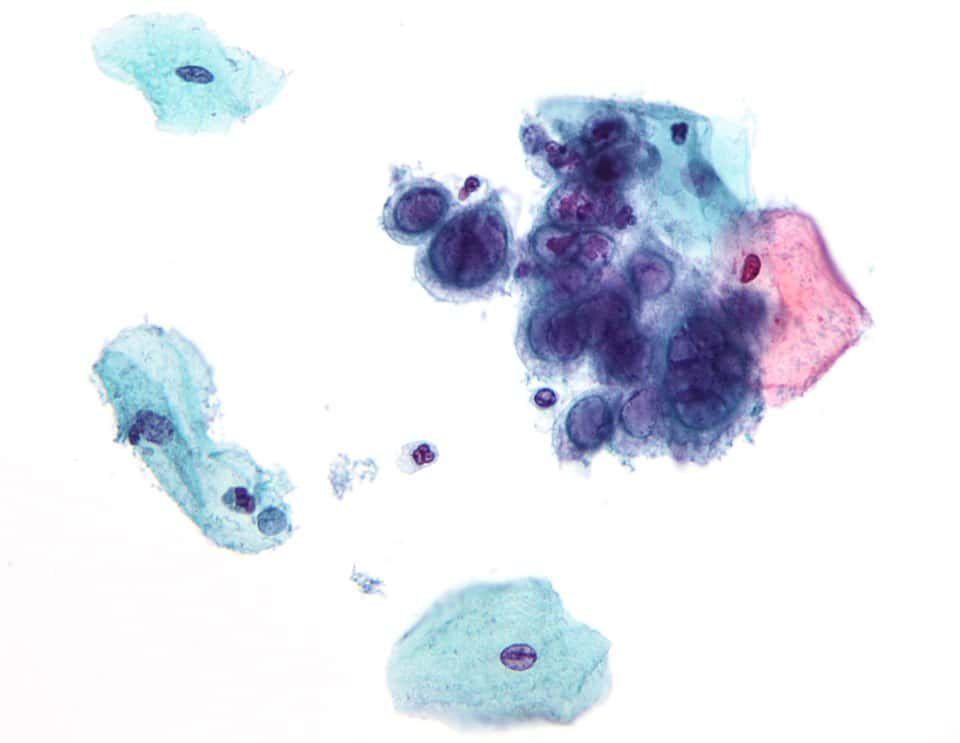

File:Herpes simplex virus pap test.jpg

| current | 04:28, 26 January 2010 |  | 2,620 × 2,028 (656 KB) | Nephron | {{Information |Description={{en|1=Micrograph showing the changes of '''herpes simplex virus (HSV)'''. Pap test. Pap stain. The changes seen above may also been seen with the '''[[ |